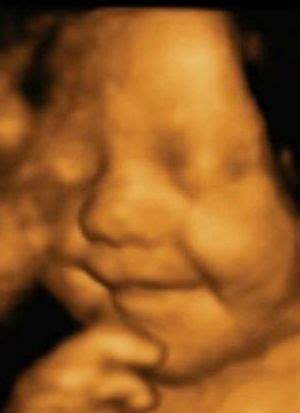

Pastaruosius kelerius metus plačiai kalbama apie 3D ir net 4D vaisiaus echoskopiją. Paklausta, ką reiškia šie skaičiai, gydytoja paaiškina: „2D - tai įprasta dvimatė echoskopija, kai ultragarso aparato ekrane ar pateiktoje nuotraukoje matomas nespalvotas dvimatis vaizdas. 3D jau leidžia sudaryti erdvinį trimatį vaizdą, kai ekrane galima stebėti ir vaisiaus veido bruožus, 4D - tai iš kelių atskirų 3D vaizdų sudarytas vienas klipas, tarsi filmukas.“